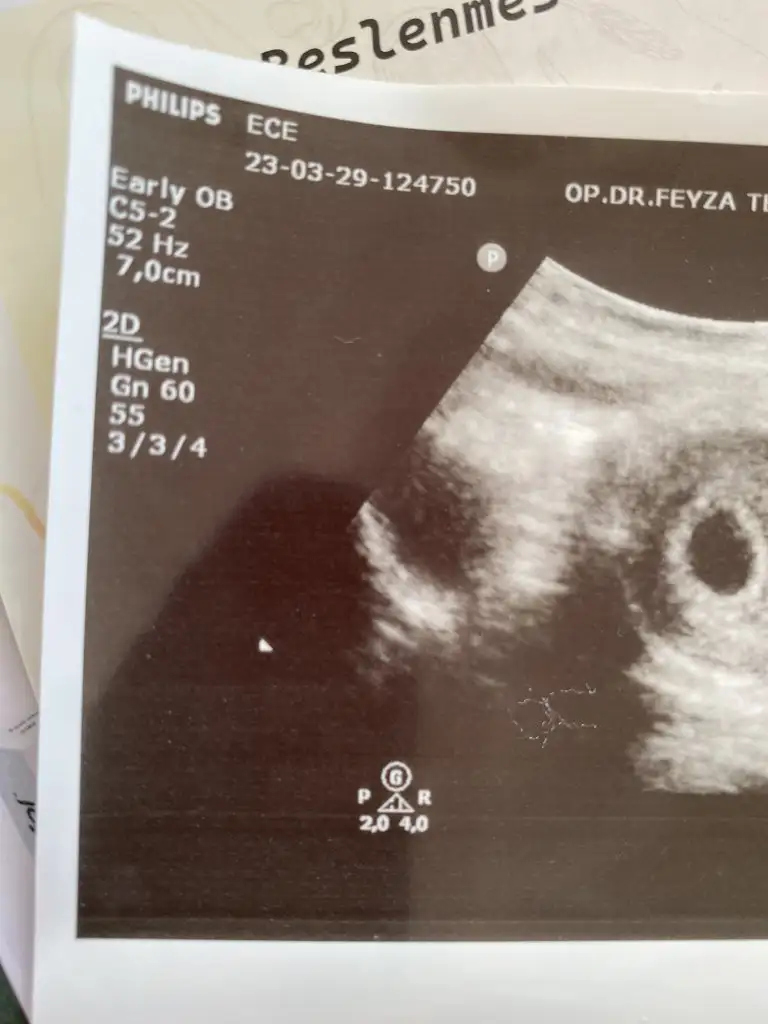

Beta 1500 üstü vajinadan kese görünüyor deniyor. Benim gittiğim gün 7000 di önce karından sonra vajinadan baktı doktor. Sadece kese göründü. Bence bidaha kan verme. Durduk yere strese giriyor insan düşük de olsa yüksek de olsa. Eğer kanaman lekelenmen yoksa bebeğin büyüyordur Allah’ın izniyle. Hesap yapıp doktor gününü ayarlayabilirsin.